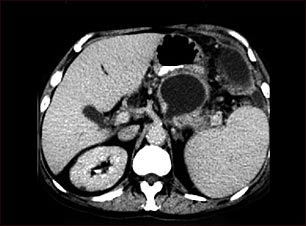

Seudoquiste pancreático, Tomografía computarizada

Esta TC del abdomen superior muestra un seudoquiste en el cuerpo o cola del páncreas.